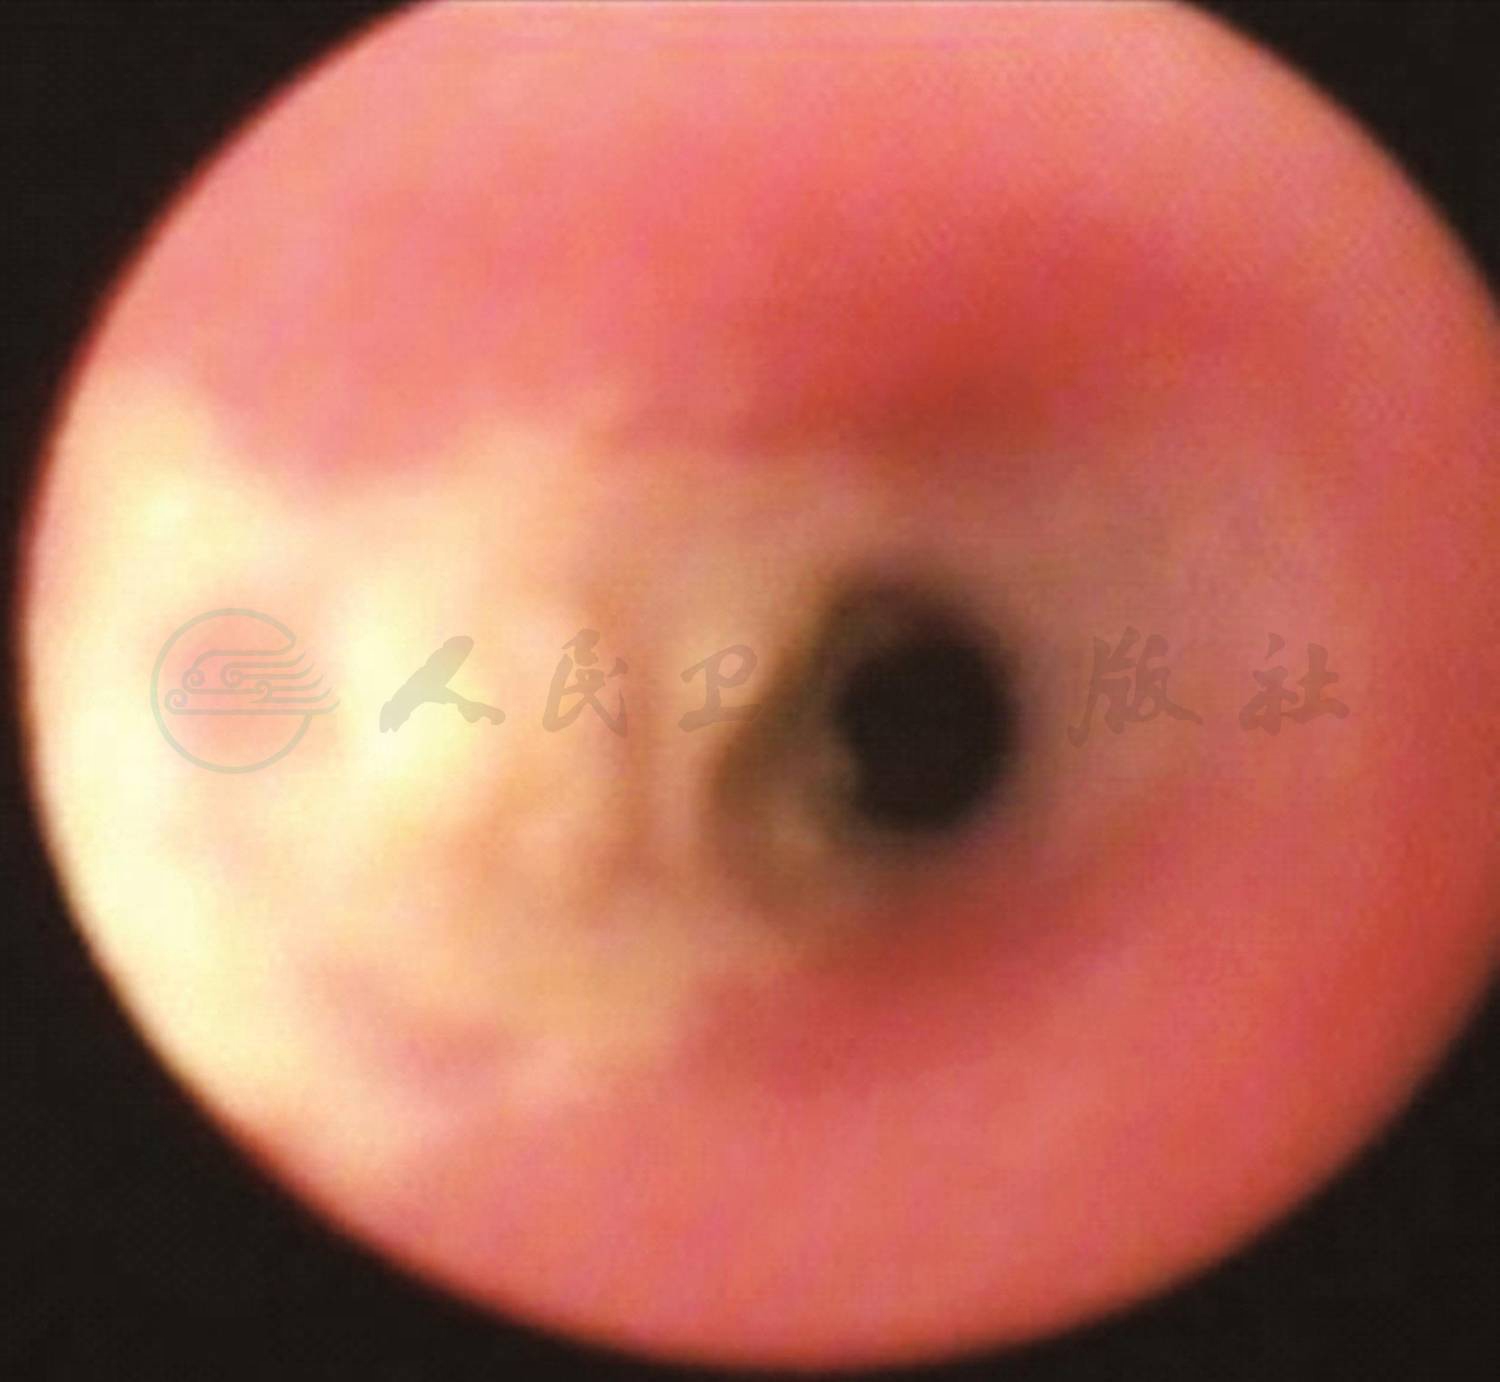

出院后13天因咳喘加重再次入院,双肺听诊可闻及中等量的湿啰音及喘鸣音,复查肺CT较前无明显改变。家属同意完善支气管镜检查,行第1次支气管肺泡灌洗术,镜下(图4)见支气管及右主支气管的黏膜有黄白色干酪样物质附壁,刷检并取肺泡灌洗液检查,未查出病原学阳性证据。3天后第2次行支气管肺泡灌洗术和活检,病理检查结果(图5)示见较多霉菌菌丝,细菌涂片见大量的真菌菌丝,疑似曲霉菌,细菌培养结果(图6)为烟曲霉菌生长。确诊为闭塞性细支气管炎合并肺曲霉菌病,遂予加用静脉滴注伏立康唑治疗[首日6mg/(kg·次),间隔12小时1次;第2天始4mg/kg,间隔12小时1次]。静滴伏立康唑1周后喘息症状较轻明显缓解,安静状态下无喘息及呼吸困难,活动后仍有喘息,改为伏立康唑片口服治疗5天(100mg/次,间隔12小时1次),喘息无加重,肺部听诊可闻及散在痰鸣音及少许喘鸣音,住院17天出院。出院医嘱:①口服伏立康唑片(100mg/次,间隔12小时1次);②口服甲泼尼龙片12mg,每天2次;③小剂量红霉素100mg/次,每天2次[5mg/(kg·d)];④乙酰半胱氨酸 600mg/次,每天 1 次口服;⑤钙尔奇 D 300mg/次,每天2次口服;⑥泵吸布地奈德0.25mg+生理盐水1ml/次,每天2次;⑦2周后门诊复查。

图4 纤维支气管镜检查镜下改变

诊断依据:①临床表现:咳嗽、喘息、反复发热近2个月,经抗生素和支气管舒张剂治疗效果不理想。②肺HRCT提示:双肺透过度不均匀,呈马赛克征改变,多叶段炎症,右肺部分实变,双肺散在肺气囊形成。③镜下见支气管及右主支气管的黏膜有黄白色干酪样物质附壁,活检病理结果示:见较多霉菌菌丝;肺泡灌洗液细菌涂片见大量的真菌菌丝,肺泡灌洗液细菌培养为烟曲霉生长。